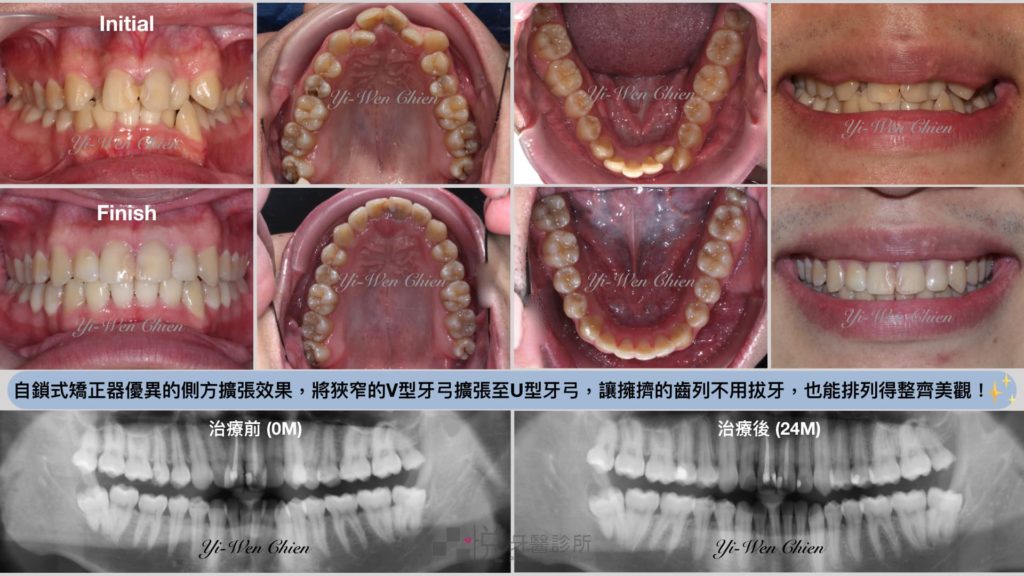

除此之外,自鎖式矯正器相較於傳統矯正器會有較少的門牙前傾以及更多的側方擴張。因此在排列擁擠凌亂的齒列時,能減少門牙前傾所帶來的嘴唇向外突出;而側方的牙弓擴張則有機會可以降低拔牙和齒間修磨的需求。